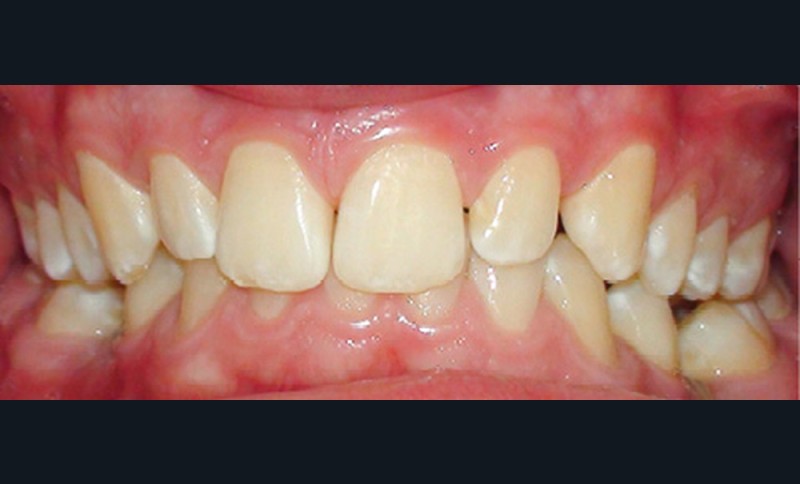

Quand un traitement orthodontique est indiqué dans le cadre de la persistance d’une molaire temporaire, l’orthodontiste doit toujours choisir entre deux solutions : maintenir ou fermer l’espace d’agénésie. Malheureusement, il est parfois confronté à une indication de maintien de l’espace d’agénésie, alors que la dent temporaire ne peut pas être maintenue jusqu’à la fin de la croissance (pour cause de caries, de réinclusion sévère, de perte, etc.) (fig. 1). La pose d’un mainteneur d’espace en fin de traitement est nécessaire, mais rien ne maintient l’os jusqu’à la fin de la croissance et la pose implantaire ! Les patients se retrouvent alors obligés de recourir à des préparations osseuses préimplantaires parfois lourdes. Le but de cet article est de proposer des solutions de maintien du volume osseux après avulsion de la deuxième molaire temporaire.